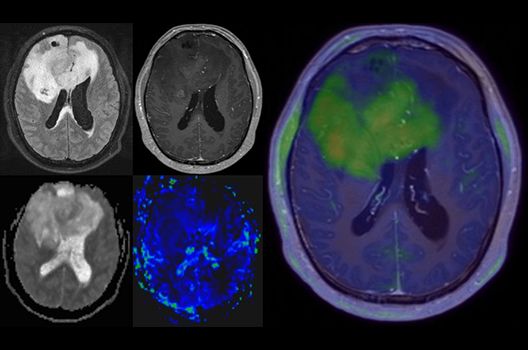

Onkologische und Hybridbildgebung

- PET/MRT in der Neuroonkologie

- Diffusion Kurtosis Imaging

- Molekulare Bildgebung mit innovativen Tracern in Kooperation mit der Nuklearmedizin und Radiopharmazie

Die Hybridbildgebung mittels PET/MRT spielt insbesondere in der onkologischen Bildgebung eine wichtige Rolle. Eine mögliche Fragestellung ist die Unterscheidung zwischen einem Tumorrezidiv oder therapeutisch assoziierten Veränderungen insbesondere dann, wenn diese Frage mittels MRT alleine nicht beantwortet werden kann.

Die bildgebende Diagnostik und Verlaufsbeurteilung von Tumoren des Nervensystems ist einer der klinischen und Forschungsschwerpunkte unserer Abteilung. Eine besondere Bedeutung kommt der Hybrid-Bildgebung zu. Das Universitätsklinikum verfügt über einen integrierten Ganzkörper-PET/MRT-Scanner, der die Vorteile der MRT-Bildgebung und der Positronenemissionstherapie (PET) vereinigt. Aufgrund der langjährigen klinischen Arbeit und Forschungstätigkeit mit diesem Gerät hat die Neuroradiologie Tübingen maßgeblich zur Etablierung dieses Verfahrens beigetragen. Auch weiterhin forschen wir intensiv an neuen Methoden zur frühen Einordnung von Tumoren und insbesondere Tumorrezidiven, die mit anderen Methoden häufig nicht erfasst werden können.